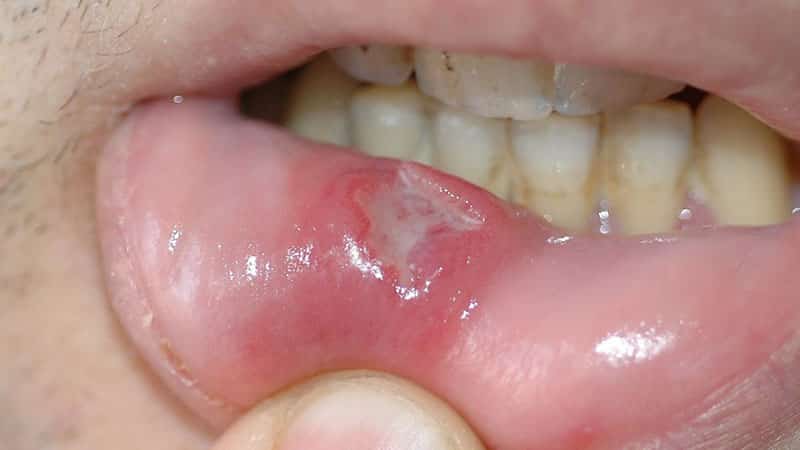

Что на счёт внешнего вида

Количество язвочек может варьироваться, как и их внешний вид. Иногда наблюдается всего одна язва, а в других случаях воспалительные процессы охватывают всю ротовую полость. В начале она выглядит как небольшая опухоль с красноватым оттенком. Затем на её поверхности образуется белесая плёнка. Такие воспаления, как афтозный стоматит или простой стоматит, характеризуются именно белым цветом. При обращении к врачу, скорее всего, вам поставят именно этот диагноз.

Даже если появилась всего одна маленькая опухоль, лечение следует начинать без промедления. В противном случае она может прогрессировать, и вскоре появятся новые образования.